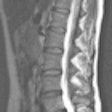

Parallel 3T MRI offers quicker spine imaging